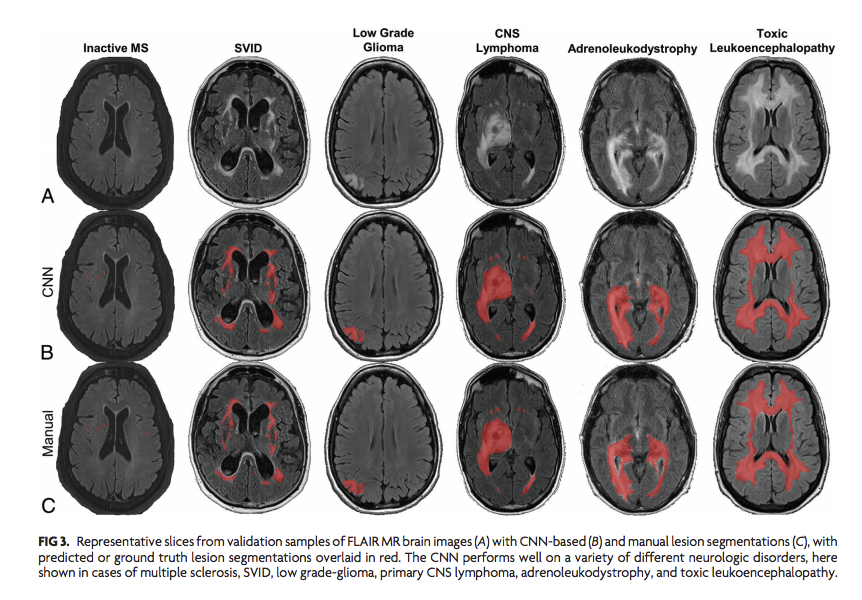

Check out our

#AI algorithm to auto-detect brain MRI lesions across many diseases. We hope this tool makes#radiology measurements more reproducible/accurate/efficient!@RadRudie@drsuyash@TheAJNR@TheASNR@theASFNR@NeuroDx@PennRadiology@UCSFimaging http://www.ajnr.org/content/early/2019/07/25/ajnr.A6138 …pic.twitter.com/vLIKGFpd7l

Convolutional Neural Network for Automated FLAIR Lesion Segmentation on Clinical Brain MR Imaging |

@DrDreMDPhD http://bit.ly/2ZtxAFj#NeuroRad#DeepLearningpic.twitter.com/d1jvMmGF54